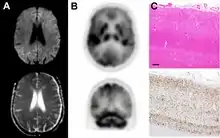

MRI of iCJD because of growth hormone

The defective protein can be transmitted by contaminated harvested human brain products, corneal grafts,[23] dural grafts,[24] or electrode[25] implants and human growth hormone.[26]

dwMRI, FDG PET and post mortem histology from a patient who presented with sCJD aged 66

Brain FDG PET-CT tends to be markedly abnormal, and is increasingly used in the investigation of dementias.

• Patients with CJD will normally have hypometabolism on FDG PET.[50]